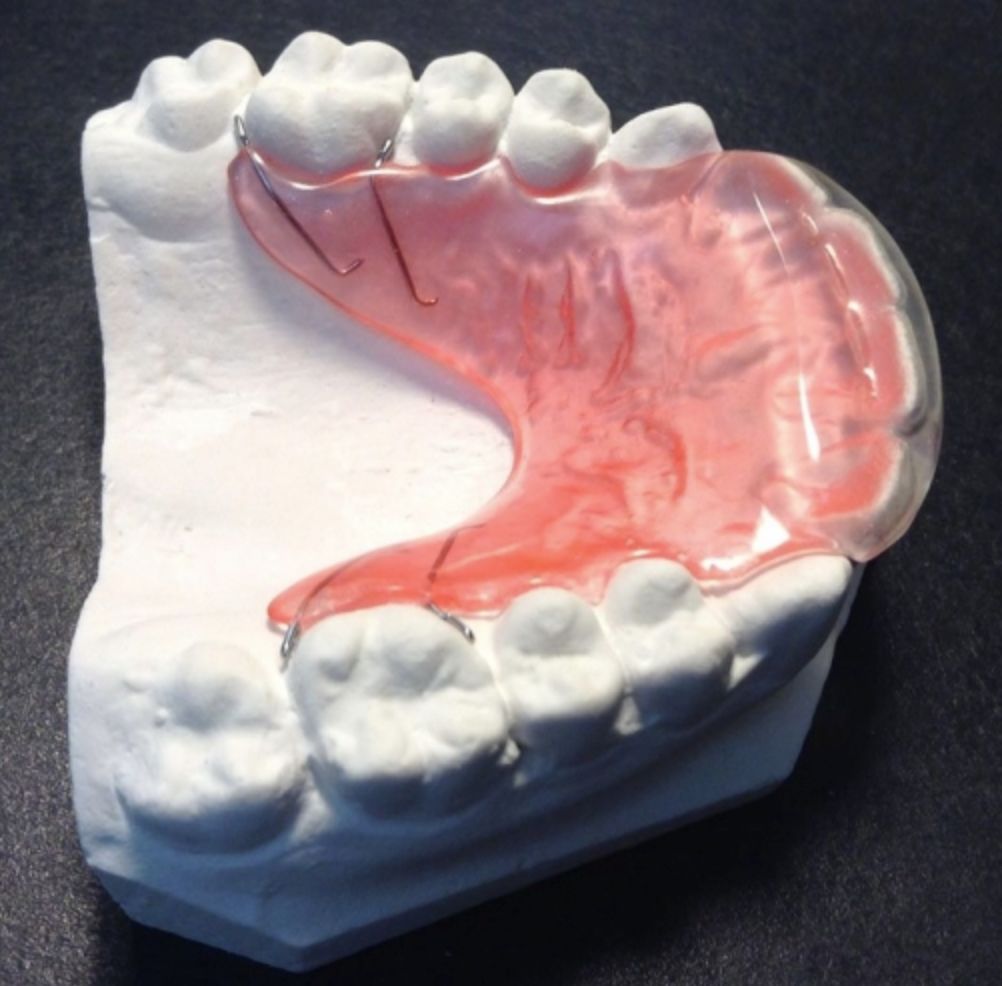

1.传统活动矫治器

患者可以自行摘戴的矫正装置,对于部分的病例,简单的活动矫治器就能达到很好的治疗效果。然而,由于活动矫治器需要自行摘戴,因此患者的配合很大程度决定了治疗的成败。